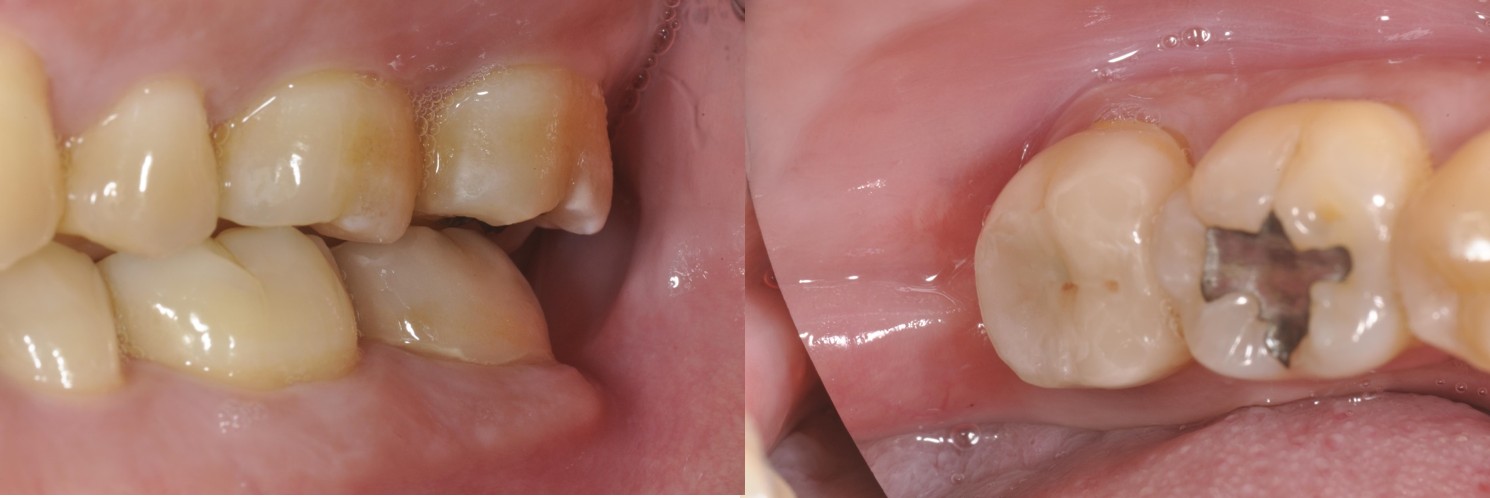

治療前,左下第二大臼齒疼痛

治療前,第二大臼齒有玻璃陶瓷全瓷冠